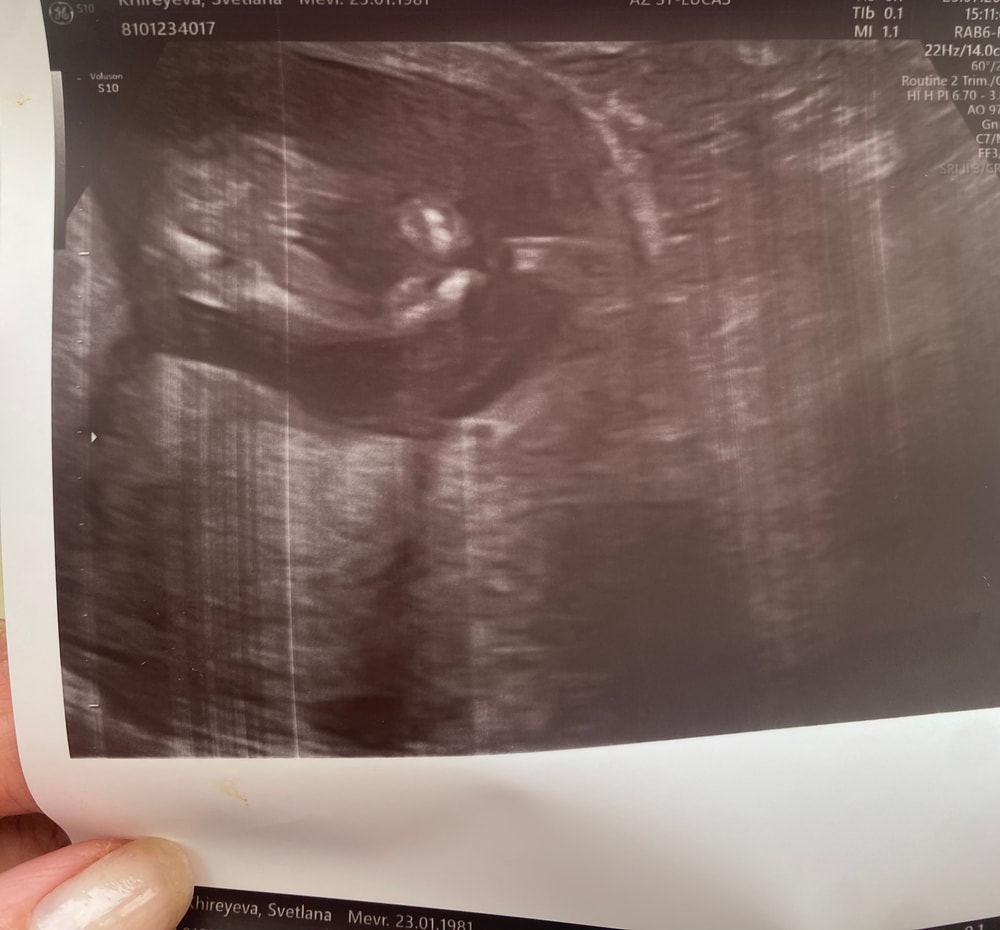

А это сегодня 14 недель⤵️ сделали снимок убедиться еще раз 😆

Ну что, так ждала этого момента, когда смело могу сделать тут запись, опубликовать пост,и вот сегодня 25/07 я с улыбкой на лице, со слезами радости, делюсь своей «ПОБЕДОЙ» Мой 11ый перенос, мой 12 по счету эмбриончик По Узи по анализам НИПТ -здоровый малыш,ну и у нас «🎀ДЕВОЧКА🎀 Мечта папина!!!Мамина душа!!! Папина радость!!! Господа Бога благодарю за все, за все испытания что он мне давал, за мое терпение,за все я благодарна в миллион раз 🥹😭🙏🙏🙏🙏 Разрыдалась сегодня прям в кабинете от счастья, с моей душевной и замечательным врачом/гинекологом мы по обнимались от радости☺️ потом посмотрели по УЗИ малышку, измерила - мы 9 см , пытались посмотреть личико но она так крутилась вертелась , головку туда сюда крутила, так смешно было, потом ручкой и ножкой стала играться, это было так милооо это было не вероятно, ребенок там уже кувыркался только так, мой доктор еще меня спросила « ты еще не чувствуешь шевелюшки» потому что она очень была подвижна+ расположение по задней стенке матки ☺️🎀 показала как бьется все четыре клапана♥️ показала все ручки ножки пальчики,сердечко слушали,все было очень радостно и я была ужасна спокойна ☺️🙏 Я только сейчас поняла , и почувствовала как можно дышать полной грудью🤭 без переживаний и волнений !!! мой беременный воздух стал сегодня другим миром !!!! Я просто нахожусь в эйфории !!!! Господи спасибо за все🙏